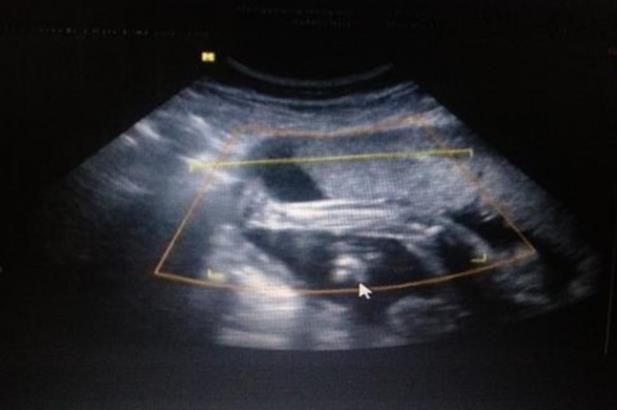

杭州自供卵精代懷 2022杭州省婦保第三代試管費(fèi)用,會(huì)不會(huì)很貴? ‘b超查男女會(huì)不會(huì)把臍帶看成是男孩’